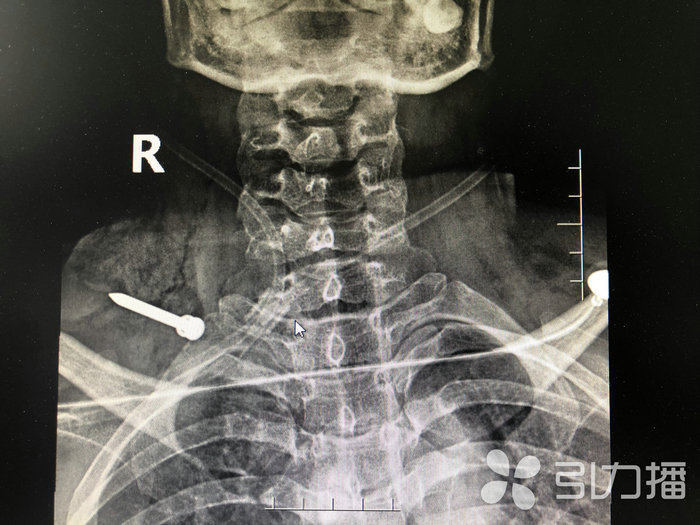

王女士立即被120送到了苏州科技城医院医院急诊部,快速完成颈部CT和X线检查。该院普外一科主任医师王奇与骨科副主任医师徐希斌立即赶往急诊进行会诊。

专家看到,王女士右颈部有一长约6厘米的伤口,伤口处还外露着一根铁钉,铁钉尖头朝外,创口内还不停出血,右侧上肢活动受限。影像资料未见明确的颈部骨结构破裂。王奇表示,需马上对其进行颈部手术探查,明确损伤情况,取出异物。

“因为颈部被高速飞行的铁钉损伤,无法确认内部受伤情况,手术必须把颈部重要血管、神经、肌肉组织显露,查看有无损伤及仔细探查伤道。经判断,王女士的右臂丛神经损伤,颈外静脉断裂,颈部肌肉多处断裂,伤道紧靠颈总动脉。但凡稍有偏差,后果将不堪设想。”王奇小心翼翼将钉子取了出来,足足有5公分长。最后经过颈部清创缝合,手术顺利,术后生命体征平稳。